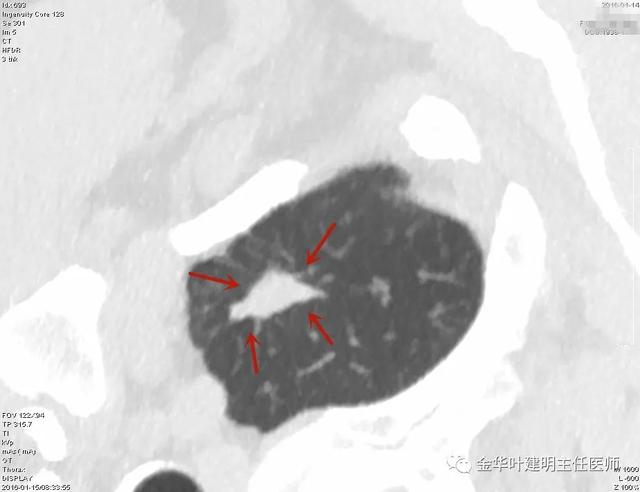

当然浸润性腺癌表现还有其他典型的一些特征,鉴于篇幅所限以及过于复杂多样,此暂不展开分析。有兴趣的朋友可关注我的了解更多影像病理分析病例。其他小细胞肺癌、神经内分泌癌表现为肺结节的相对少些,暂不再展开分析了。实性结节难就难在,不同的疾病可都表现为肺结节影,我们来看下面的图像,谁能从影像上来分辨其到底是什么疾病呢:

叶建明谈结节:检查发现肺实性结节怎么办?个人版实用指南

上图是肺泡上皮增生

上图示结核

上图是浸润性腺癌

上图是肺内淋巴结

上图是鳞癌

上图是纤维增生

上图是隐球菌

这些病例中的结节,你说哪有很大的影像区别或与其实际疾病的特征呢?其实都很难判断出来,只知道是实性结节,有的偏大点,有的小的,密度都比较高。也有些时候,又是像下面这种情况: